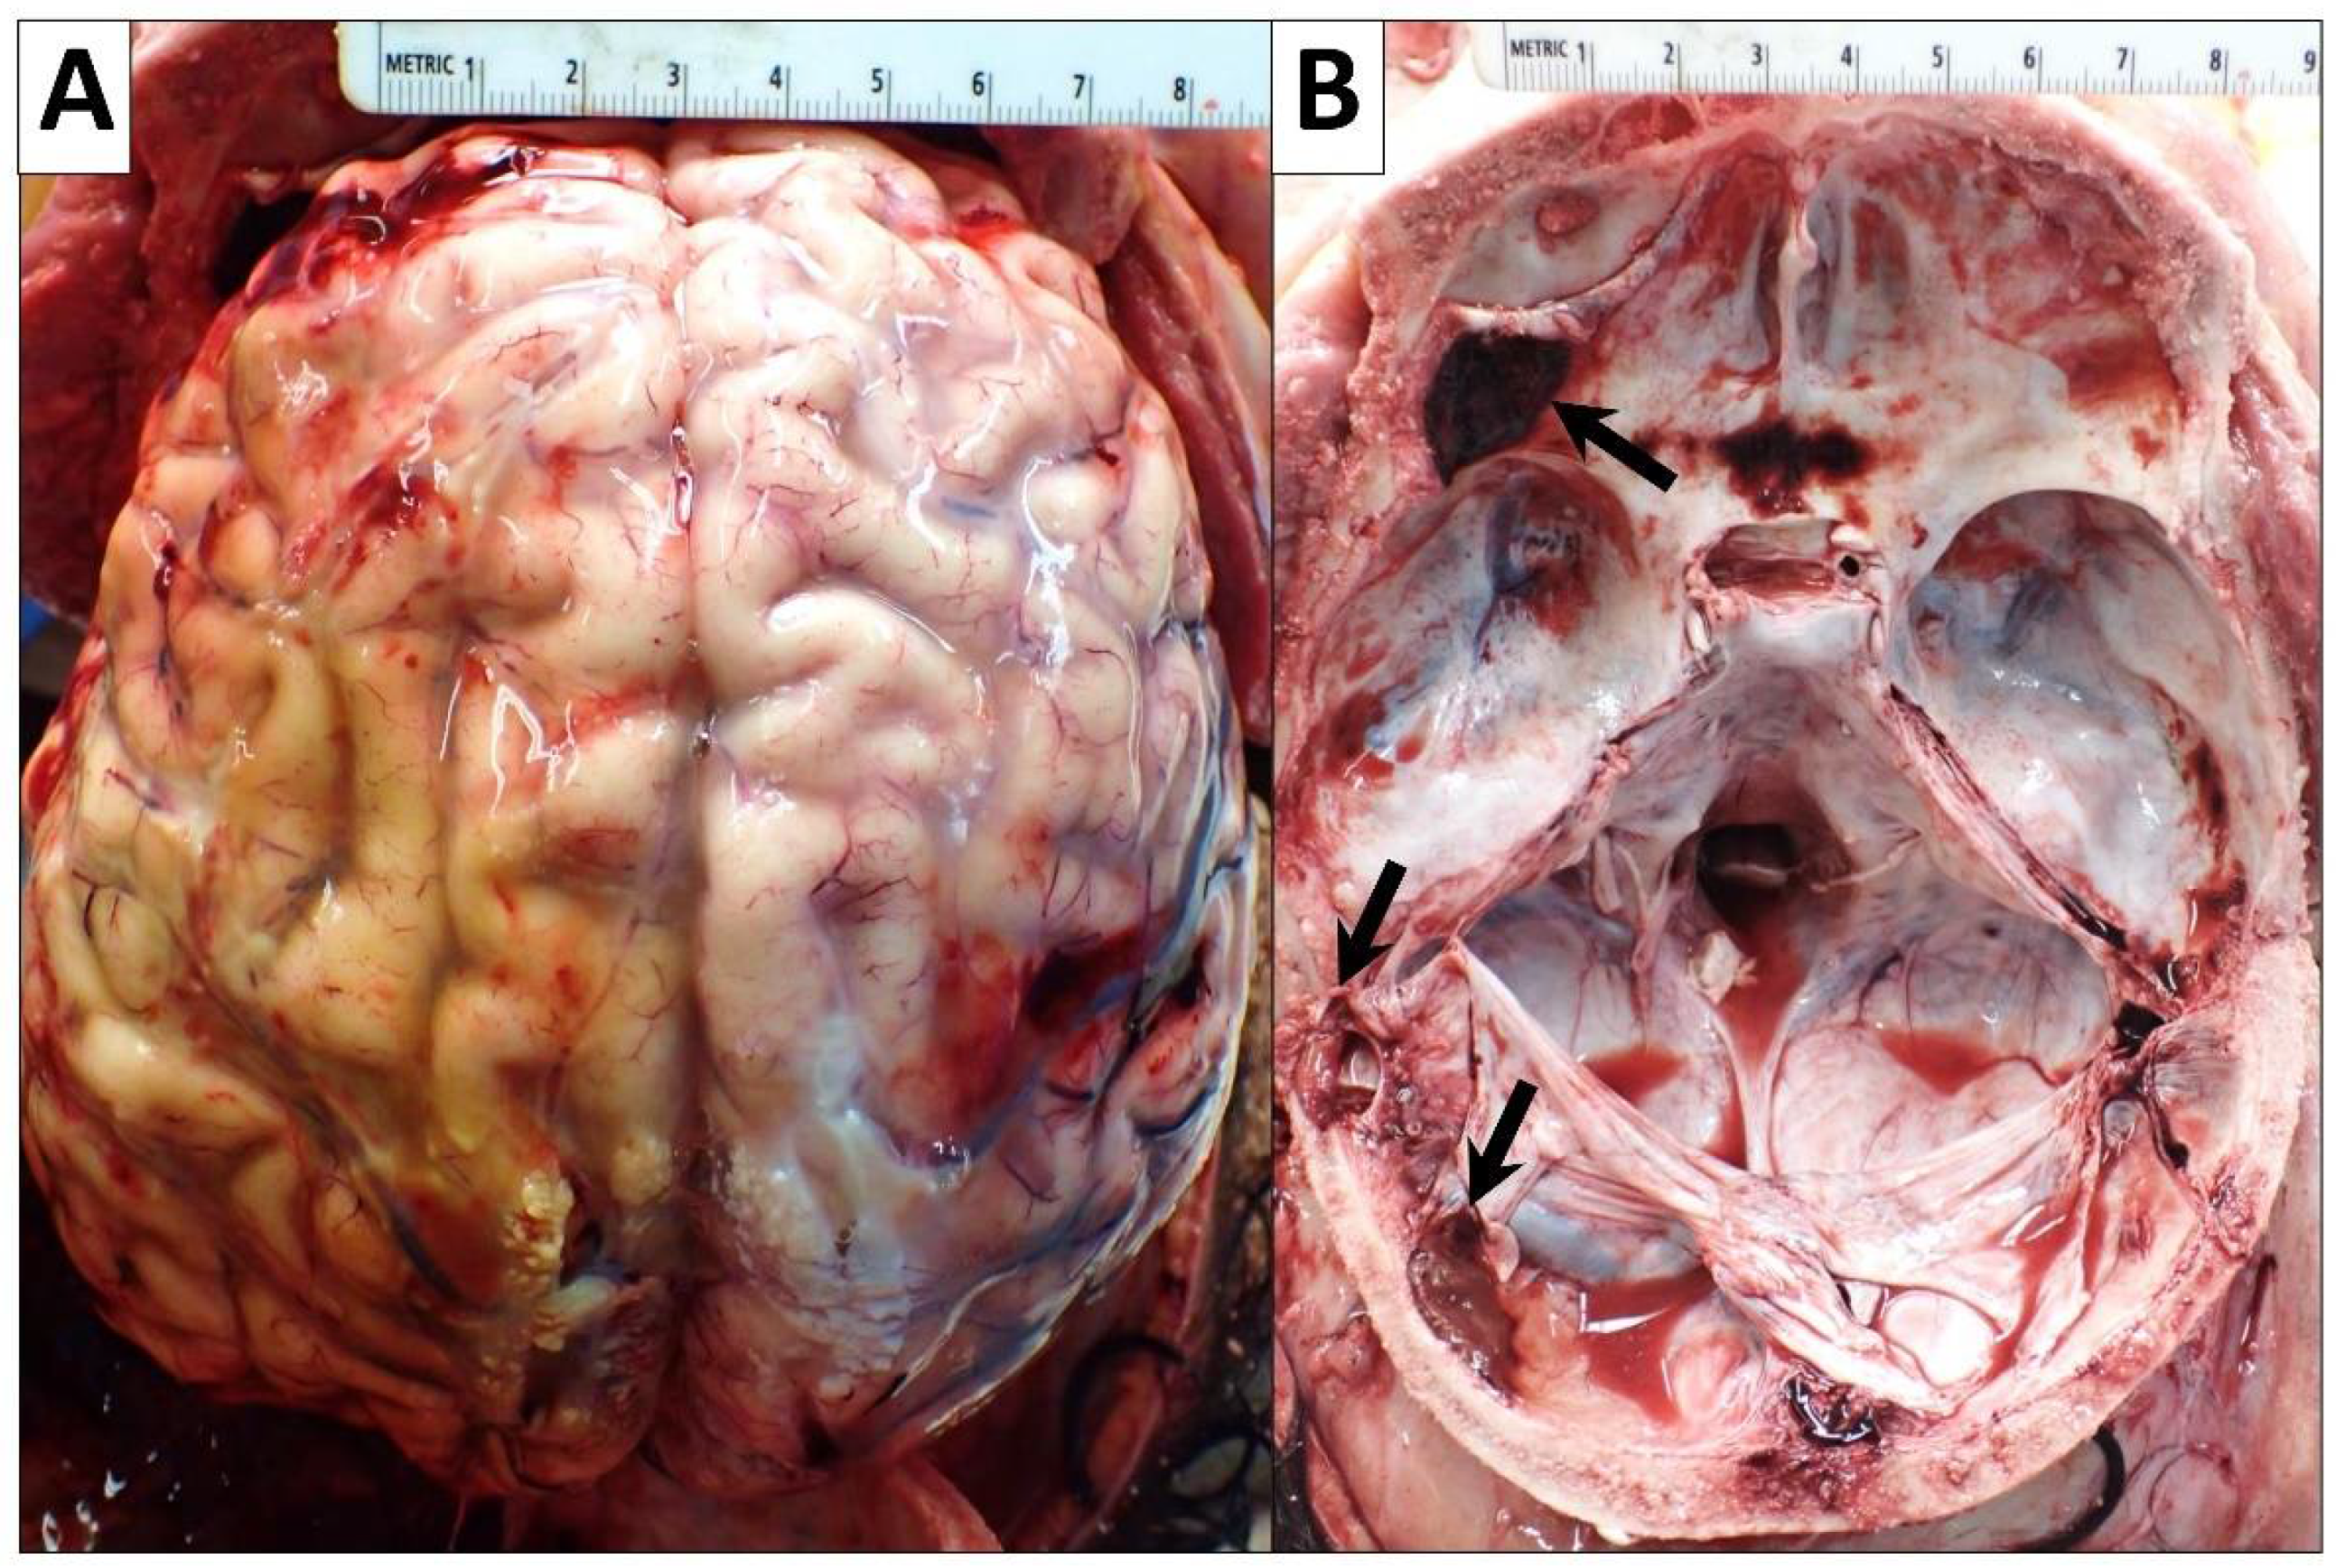

2.2.7. Central Nervous System